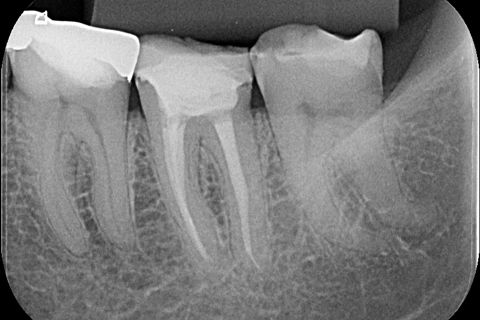

O caso clínico abaixo mostra a utilização do cimento MTA Fillapex (Angelus) associados a cones de guta percha para a obturação endodôntica de um caso de tratamento endodôntico realizado em sessão única.

Após 17 meses a paciente compareceu para consulta de controle e na radiografia foi possível observar sucesso endodôntico caracterizado por ausência de sinais e sintomas, dente em função fisiológica, normalidade do periápice e reabsorção do surplus de MTA Fillapex.